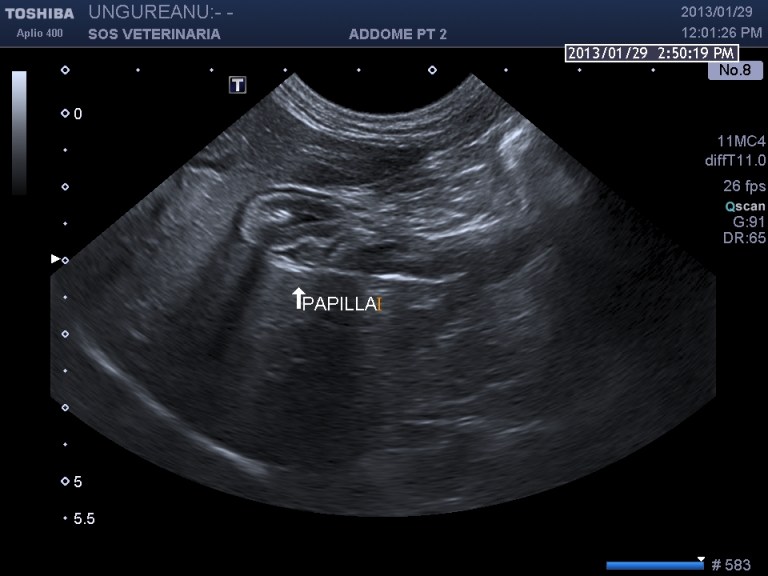

“Diverse scansioni possono essere utilizzate allo scopo di visualizzare le vie biliari extraepatiche: attraverso sezioni trasversali ed oblique a livello dell’11°-12° spazio intercostale destro, tramite scansioni ventrali longitudinali e trasversali, o attraverso la scansione cranioventrale obliqua destra (Santilli R.A. e coll., 1993; Léveillé R. e coll., 1996). Come per il condotto cistico, nella valutazione ecografica del coledoco è possibile osservare: -il diametro, che nei soggetti sani risulta ≤ 4 mm nel gatto, mentre nella specie canina misura 1-3 mm; -la forma; -il contenuto; -l’ecogenicità e lo spessore della parete (Gaillot H.A. e coll, 2007; Léveillé R. e coll, 1996; Brinkman-Ferguson E.L. e coll., 2009).

Durante l’esame delle strutture biliari può venire identificata la papilla duodenale le cui dimensioni, nei gatti sani, variano dai 2,9 a 5,5 mm in larghezza ed una massima altezza di 4,0 mm, in sezione trasversa; nel cane le sue dimensioni sembrano essere maggiormente variabili, in relazione alle differenze di peso e di razza (Center S.A., 2009).”

scansione trasversale papilla

scansione sagittale paipilla